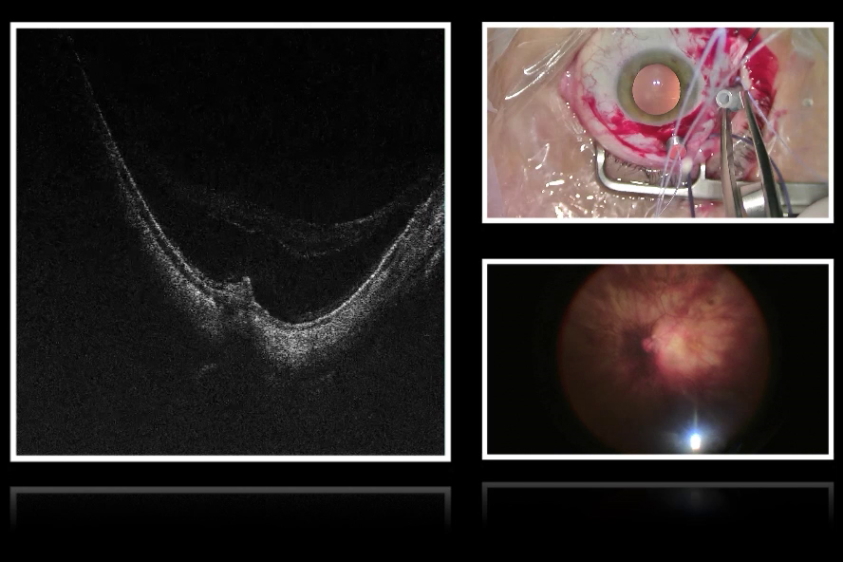

明亮稳定的红光反射对于区分患者晶状体结构至关重要。这种辨识能力使眼科医生能够在切割角膜、破碎并摘除白内障以及定位人工晶体时精准操作。红光反射由视网膜反射的光线形成,当光线垂直照射视网膜时反射效果最佳。以 M822 眼科显微镜为例,其采用双同轴光路设计,而 Proveo 8 眼科显微镜则配备四同轴光路系统以实现最佳反射条件。

Proveo 8 搭载的 CoAx4 照明系统所提供的红光反射,是徕卡眼科显微镜家族中最明亮稳定的。即便在低照度条件下,所有徕卡眼科显微镜仍能保持明亮的红光反射。鉴于照明技术存在多样性,建议始终通过比较红光反射质量来评估显微镜性能。

若眼科医生希望根据需求灵活调节对比度增强或减弱,选择具备可调红光反射照明直径的显微镜至关重要。较大直径可补偿眼球运动带来的影响,而较小直径则能减少巩膜反光并增强手术中的对比度。例如,Proveo 8 提供的可调直径范围为 4 至 23 毫米。

若诊所计划开展教学工作,集成更全面的文档记录功能或教学辅助设备(如供学员观看的示教系统)将变得尤为重要。为此,3D 可视化技术正日益普及。"抬头手术"模式无需依赖双目镜,可通过屏幕实现护理人员教学。值得关注的是,眼科显微镜能否兼容 3D 可视化系统。例如,Leica Microsystems 的 M822 和 Proveo 8 眼科显微镜可与爱尔康公司的 NGENUITY® 3D 可视化系统配合使用,使教学体验实现质的飞跃。